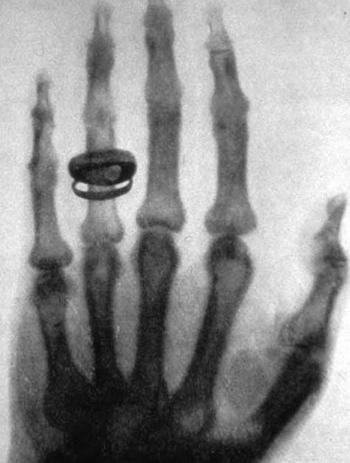

Жінка всіляко підтримувала чоловіка. Коли той довго перебував y лабораторії, Анна приносила йому обіди. Ставила їжу на столі перед дверми кімнати. Під час дослідження Рентґен нікого не впускав y лабораторію. Коли вчений закінчив своє дослідження, дозволив дружині увійти в лабораторію. Він зробив перший в історії рентгенівський знімок. Знімок кисті руки фрау Берти за кілька днів обійшов увесь світ.